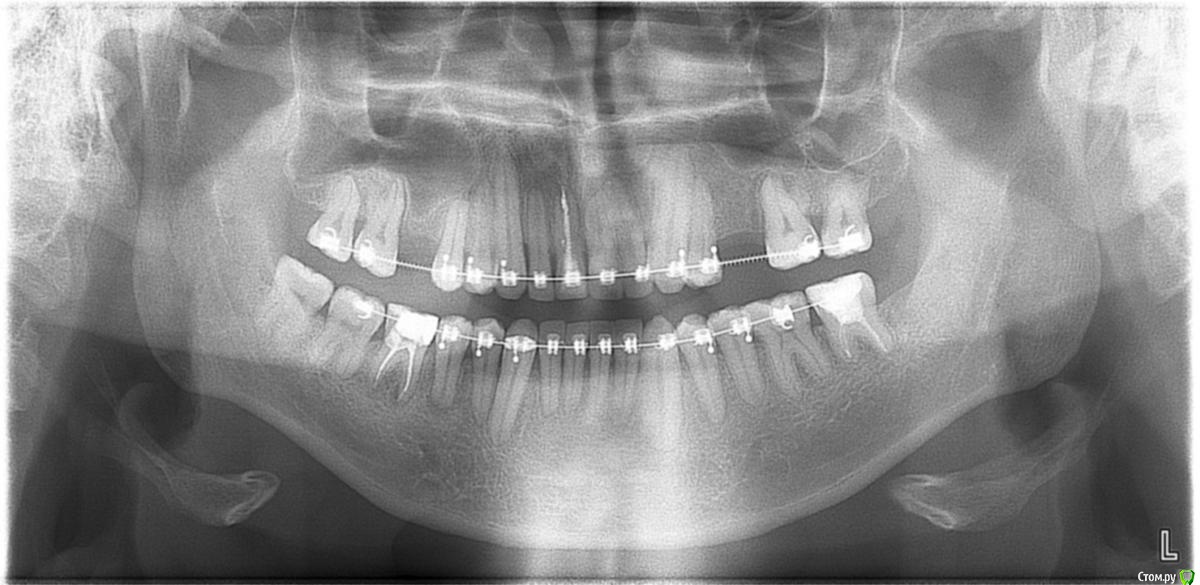

Nick-ev Опубликовано 31 марта, 2018 Автор Поделиться Опубликовано 31 марта, 2018 нужно смотреть фото/снимки Единственное что нашел май 2016 года, как раз удален левый зуб мудрости и зубы начали уходить в его сторону. а это что было до брекетов октябрь 2013 года... Ссылка на комментарий